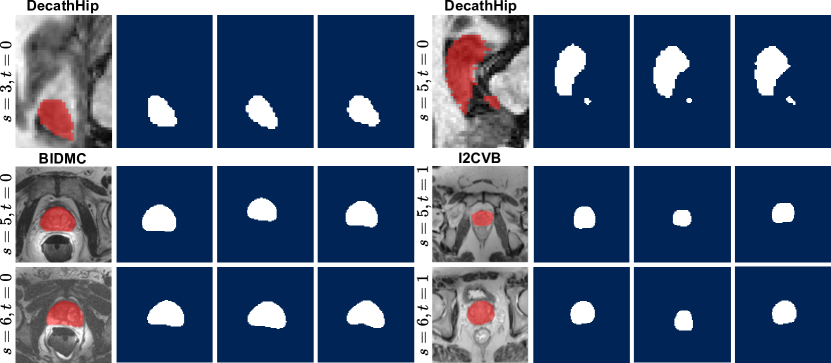

Data: Following previous work on medical continual segmentation [9, 10, 28, 27], we evaluate on the tasks of segmenting the prostate and hippocampus in, respectively, T2-weighted and T1-weighted MRIs. The hippocampus data consists of three datasets: Multi-contrast submillimetric 3 Tesla hippocampal subfield segmentation (Dryad) [19], Harmonized Hippocampal Protocol dataset (HarP[36] and the hippocampus data released for the Medical Segmentation Decathlon (DecathHip[1]. We train in the order DecathHip\rightarrowDryad following the setup in previous works [8]. We preserve HarP for OoD testing. The sets contain 260, 50, and 270 samples, respectively. The prostate data originates from five institutions using different devices and acquisition parameters [23]. We train in the order BIDMC\rightarrowI2VCB\rightarrowHK\rightarrowUCL, creating a challenging setting by starting with the smallest dataset and alternating between datasets with and without an endorectal coil. The segmentation mask encompasses the central gland and peripheral area. We likewise use the final dataset, RUNMC for OoD evaluation. Each dataset contains 12 to 30 samples and is randomly divided into 20%percent2020\% testing, 56%percent5656\% training, and 24%percent2424\% validation. A qualitative comparison of the data used can be found in Fig. 2. We also utilize synthetic OoD data. Here, we augment the test sets with common MRI artifacts (random bias field, spiking, or ghosting) doubling their size. A few examples of augmented MRIs are depicted in Fig. 3.

Figure 2: Representative slices s𝑠s of MRI scans from each (a) hippocampus and (b) prostate dataset. The red areas depict the ground truth segmentation masks.